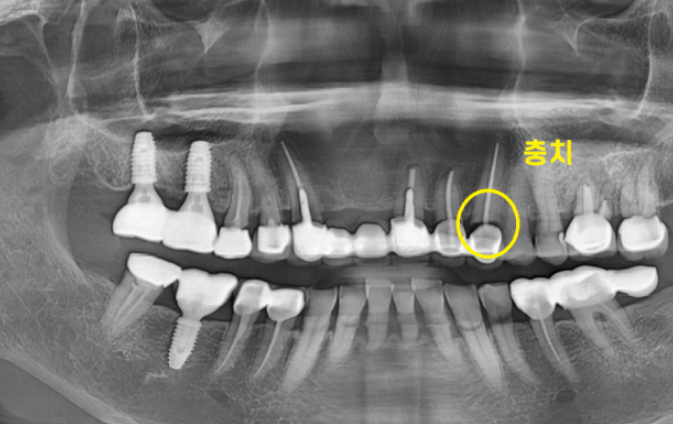

원인을 발견하기 위해 X-RAY를 촬영해보았습니다.

왼쪽 송곳니 치아 치근 우식이 관찰됩니다.

뿌리쪽 부분이 많이 썩어

치아가 끊겨진것처럼 보이실겁니다.